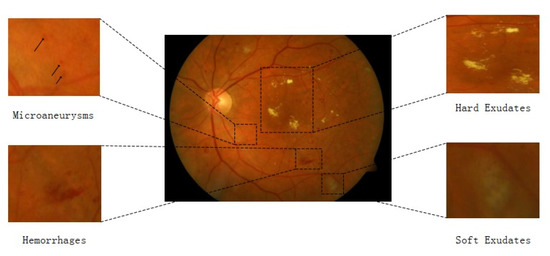

Clinicians, radiologists, and healthcare personnel use these gold-standard techniques to diagnose various diseases. However, these techniques are prone to error and are time-consuming. In addition, the data are annotated by medical domain experts who anticipate the outcomes manually. In cases of the non-availability of domain experts or the presence of unskilled healthcare personnel, a wrong interpretation of the image may cause severe problems for the patient. Therefore, it is essential to improve and develop an efficient model to assist radiologists, clinicians, and other medical staff in analyzing and diagnosing different mortal diseases [2,3]. Decreasing insulin production can result in a common medical condition termed diabetes mellitus (DM). DM may be type 1 or 2. The pervasiveness of type-2 diabetes in diabetic patients has been shown to be 90%. The prevalence of type 2 can cause other diabetic diseases, such as DR. DR is a chronic disease, and if left unattended, it may lead to severe eye conditions such as retinal detachment or blindness. It is one of the leading causes of blindness and is generally found in patients aged 20 to 65. The ophthalmologist has classified DR into five main classes, including Class 0 (no DR), Class 1 (mild), Class 2 (moderate), Class 3 (severe), and Class 4 (proliferative DR) [4,5,6]. The formation of various forms of lesions on the retina of the eyes recognizes DR. The different types of lesions are microaneurysms (MA), hemorrhages (HM), soft exudates, and hard exudates. MA is a small red round dot that appears as a lesion size less than 125 µm, while HM is a large red dot of size 125+ µm. Similarly, neovascularization is another lesion that is severe and can lead to retinal detachment. Class 0 means a normal eye or a patient with no DR. Class 1 patients have a single MA lesion, while Class 2 patients have more than one MA lesion.

DR is mostly diagnosed manually by inspecting the retinal images. The process is time-consuming and challenging since some lesions in the retinal image are tiny or subtle, such as microaneurysms illustrated in Figure 2. Many automatic or semi-automatic approaches used in CV and machine learning algorithms have been applied to increase the efficiency and accuracy of DR classifications. Before the advent of deep learning (DL) algorithms, feature extraction was a mandatory step in image classification, as in conventional CV methods. These features contain some specific and very important information about the image. Many feature extraction algorithms were proposed in the 1990s, such as SIFT [15] and SURF [16], which have been widely applied for object recognition and MIA [2]. The manually extracted features are excessively defined, incomplete, or require a long time and skill to construct and test when using traditional CV methods for DR lesion identification or classification. Instead of manual feature extraction for DR screening, many researchers are now focusing on end-to-end DL models that automatically learn all the needed features.

Figure 2. Annotated results of an image with DR [4].